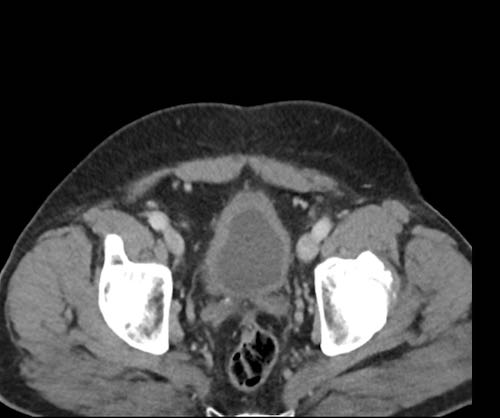

Ở vùng chậu, vị trí quan trọng nhất là túi cùng trực tràng-tử cung và trực tràng-bàng quang (túi cùng Douglas).

Đôi khi có thể thấy di căn khối u lan ra phía trước bàng quang, nhưng không xâm lấn thành bàng quang, do bàng quang là cơ quan nằm ngoài phúc mạc.

Tuy nhiên, vòm bàng quang phía trên và ống niệu rốn được ngăn cách với khoang bụng bởi một lớp phúc mạc thành, tạo thành đích tiềm năng cho các tế bào khối u.

Đặc biệt khi bàng quang đầy, các tổn thương di căn phúc mạc có thể được quan sát thấy ở phía trước bàng quang, áp sát thành bụng trước.

Đây không phải là bệnh lý quanh bàng quang, vì khoang quanh bàng quang nằm ngoài phúc mạc và không thông với khoang trong phúc mạc.